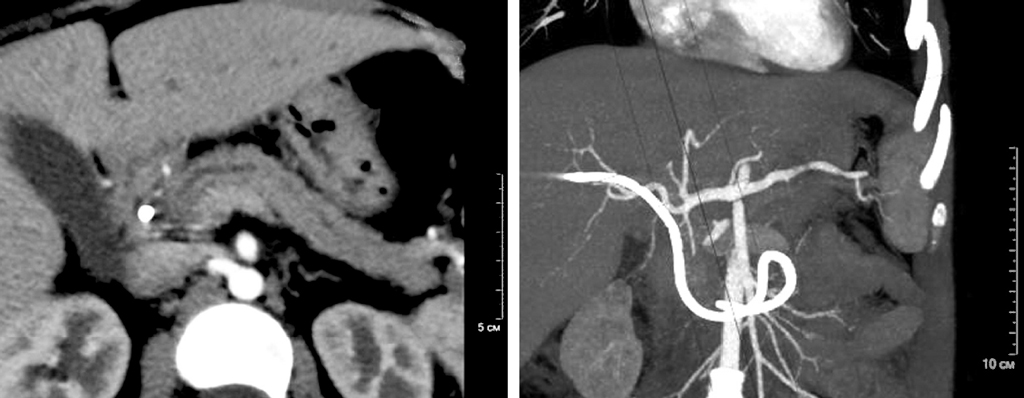

Затем вновь отмечалось появление болевого синдрома. Повторно проведено УЗИ, на котором было выявлено образование в области головки ПЖ (рис. 1) и расширение вирсунгова протока (рис. 2). От госпитализации в городскую больницу мать отказалась.

Рис. 1. Ультразвуковое исследование органов брюшной полости ребенка с аутоиммунным панкреатитом: опухолевидное образование поджелудочной железы

Fig. 1. Ultrasound examination of abdominal cavity organs of a child with AIP: tumor-like formation of pancreas

МСКТ: в проекции головки ПЖ прослеживается округлое патологическое образование с нечеткими, неровными контурами, окруженное сосудами, размерами 30 × 40 × 60 мм. Мезентериальные и парааортальные лимфатические узлы не увеличены.

МРХПГ: МР-признаки обструкции холедоха и вирсунгова протока вследствие патологического образования головки ПЖ. Холедох расширен до 13,5 мм. Вирсунгов проток расширен до 5,0 мм (рис. 2, 3).